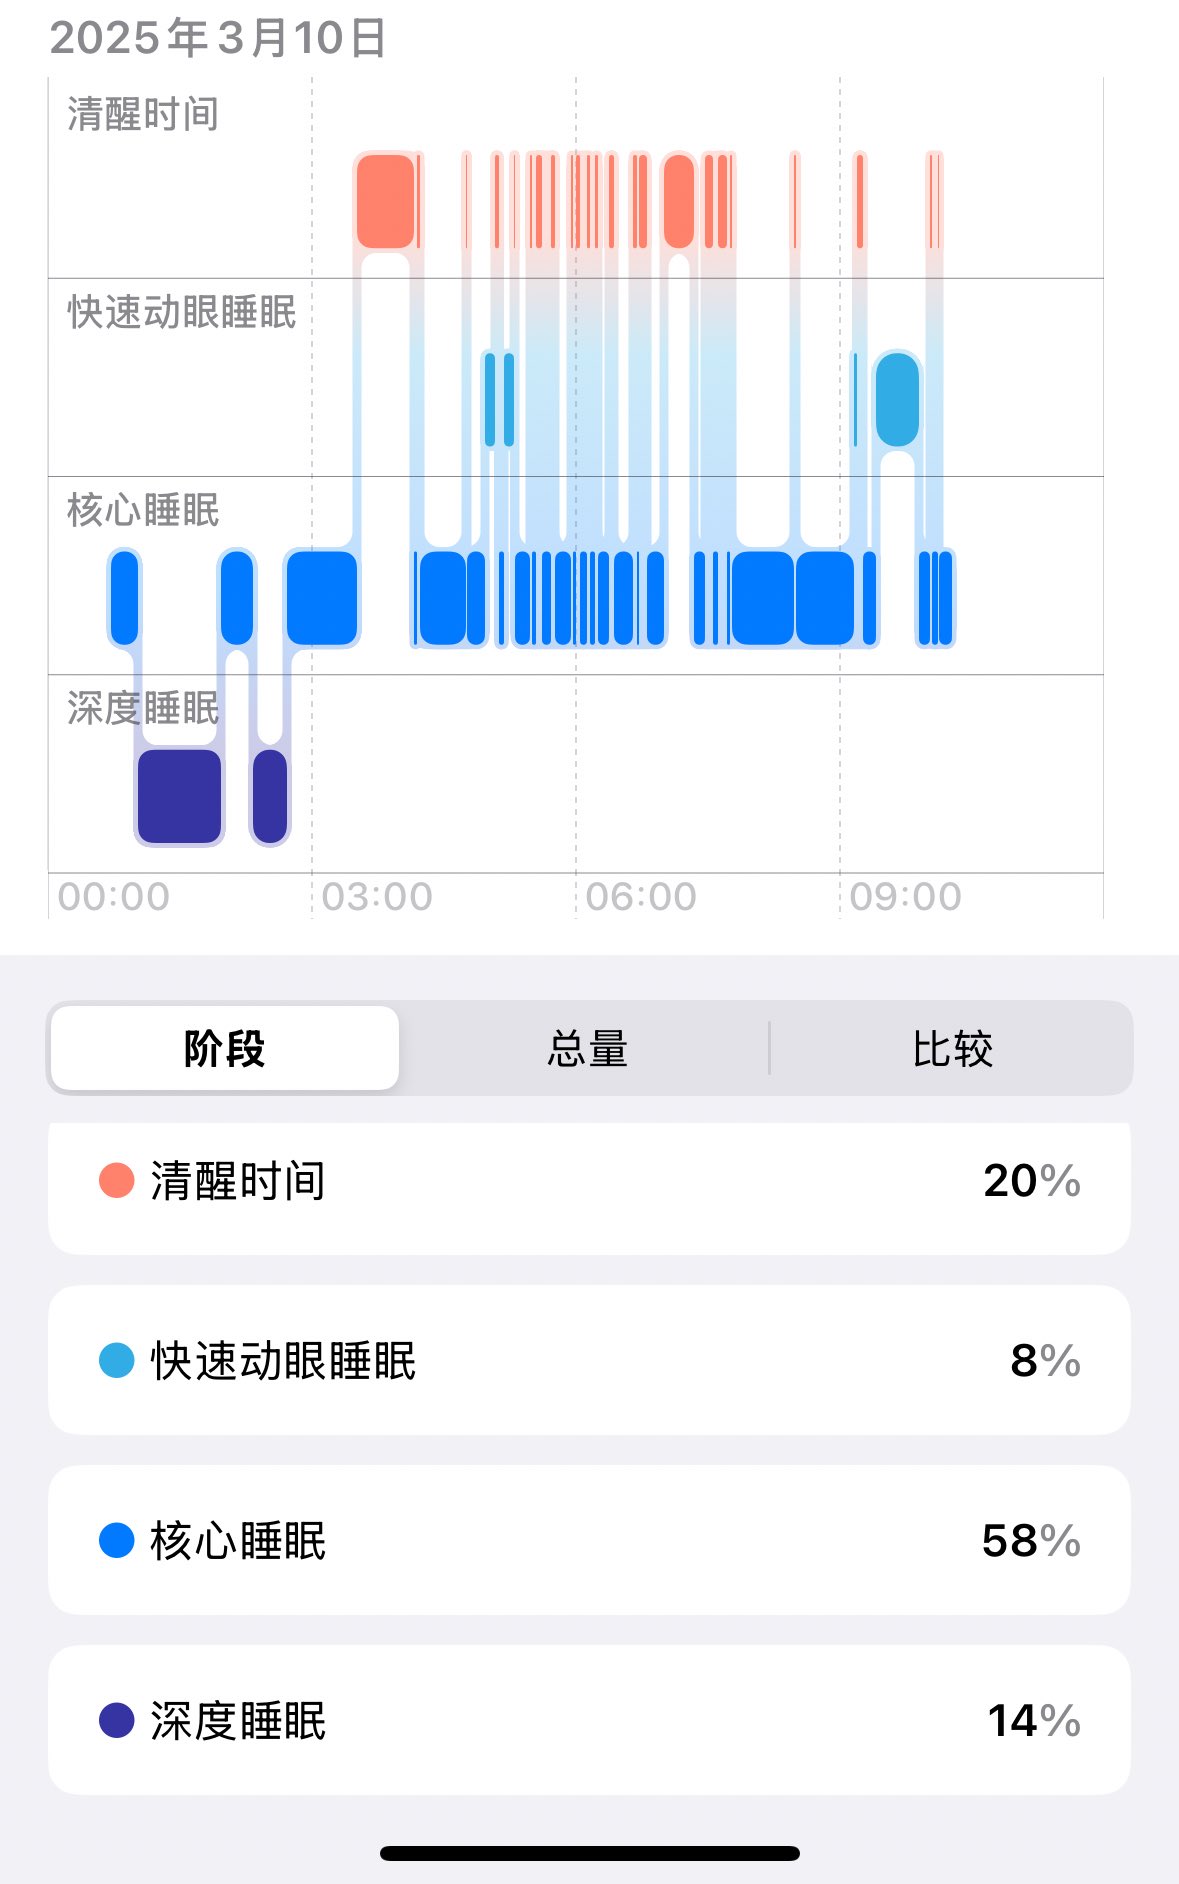

此剂量下对睡眠的改善作用,增加了慢波睡眠且没有影响rem,精力恢复+